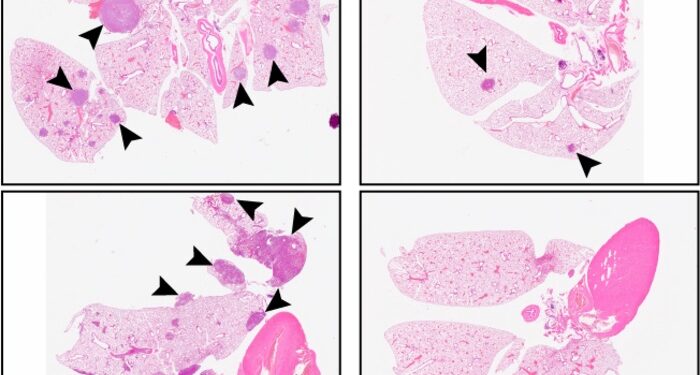

A continuación, los investigadores comprobaron si el C26 evitaría la metástasis en ratones. Los animales a los que se les inyectan células de HNSCC derivadas de pacientes suelen formar grandes tumores primarios que se extienden a los pulmones tras la extirpación quirúrgica del tumor original.

El tratamiento con C26 redujo el tamaño de los tumores primarios y, tras la cirugía, nuevas dosis de C26 bloquearon completamente el crecimiento de los tumores metastásicos. En cambio, los pulmones de los roedores sólo contenían unas pocas células cancerosas diseminadas e inactivas, incapaces de proliferar incluso tras el cese del tratamiento.